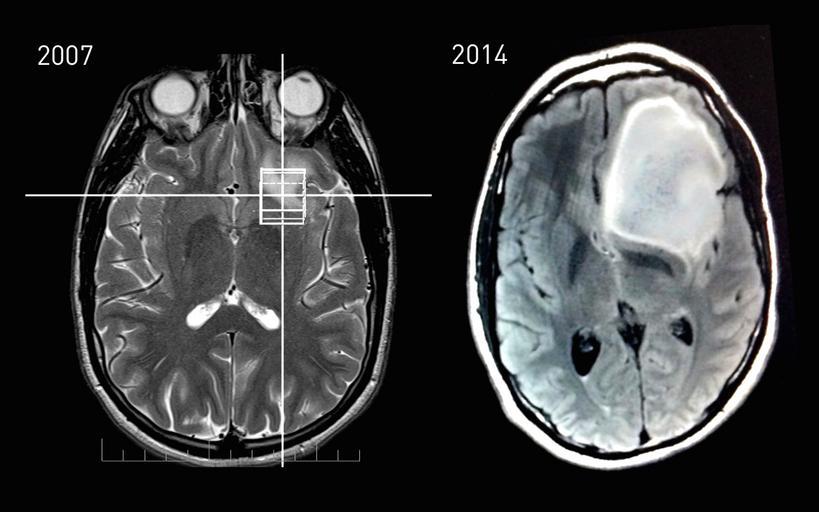

MAKE A MEME View Large Image Slices - 2007 and 2014 of astrocytoma patient - Steven Keating.jpg en MRI cranial slices showing astrocytoma tumor growth between 2007 and 2014 Scans taken at Queen's University 2007 and at Mt Auburn 2014 Patient was born in 1988 Uploaded ...

Keywords: MRI Slices - 2007 and 2014 of astrocytoma patient - Steven Keating.jpg en MRI cranial slices showing astrocytoma tumor growth between 2007 and 2014 Scans taken at Queen's University 2007 and at Mt Auburn 2014 Patient was born in 1988 Uploaded with patient approval patient Steven Keating More information on patient details available at www stevenkeating info 2015-01-15 11 16 08 Keating Steven 2014 MRI cranial slices of astrocytoma patient in 2007 and 2014 Zenodo doi 10 5281/zenodo 16852 Keating Steven 2014 other versions cc-zero Uploaded with UploadWizard Brain neoplasms Magnetic resonance imaging of the brain Media from Zenodo